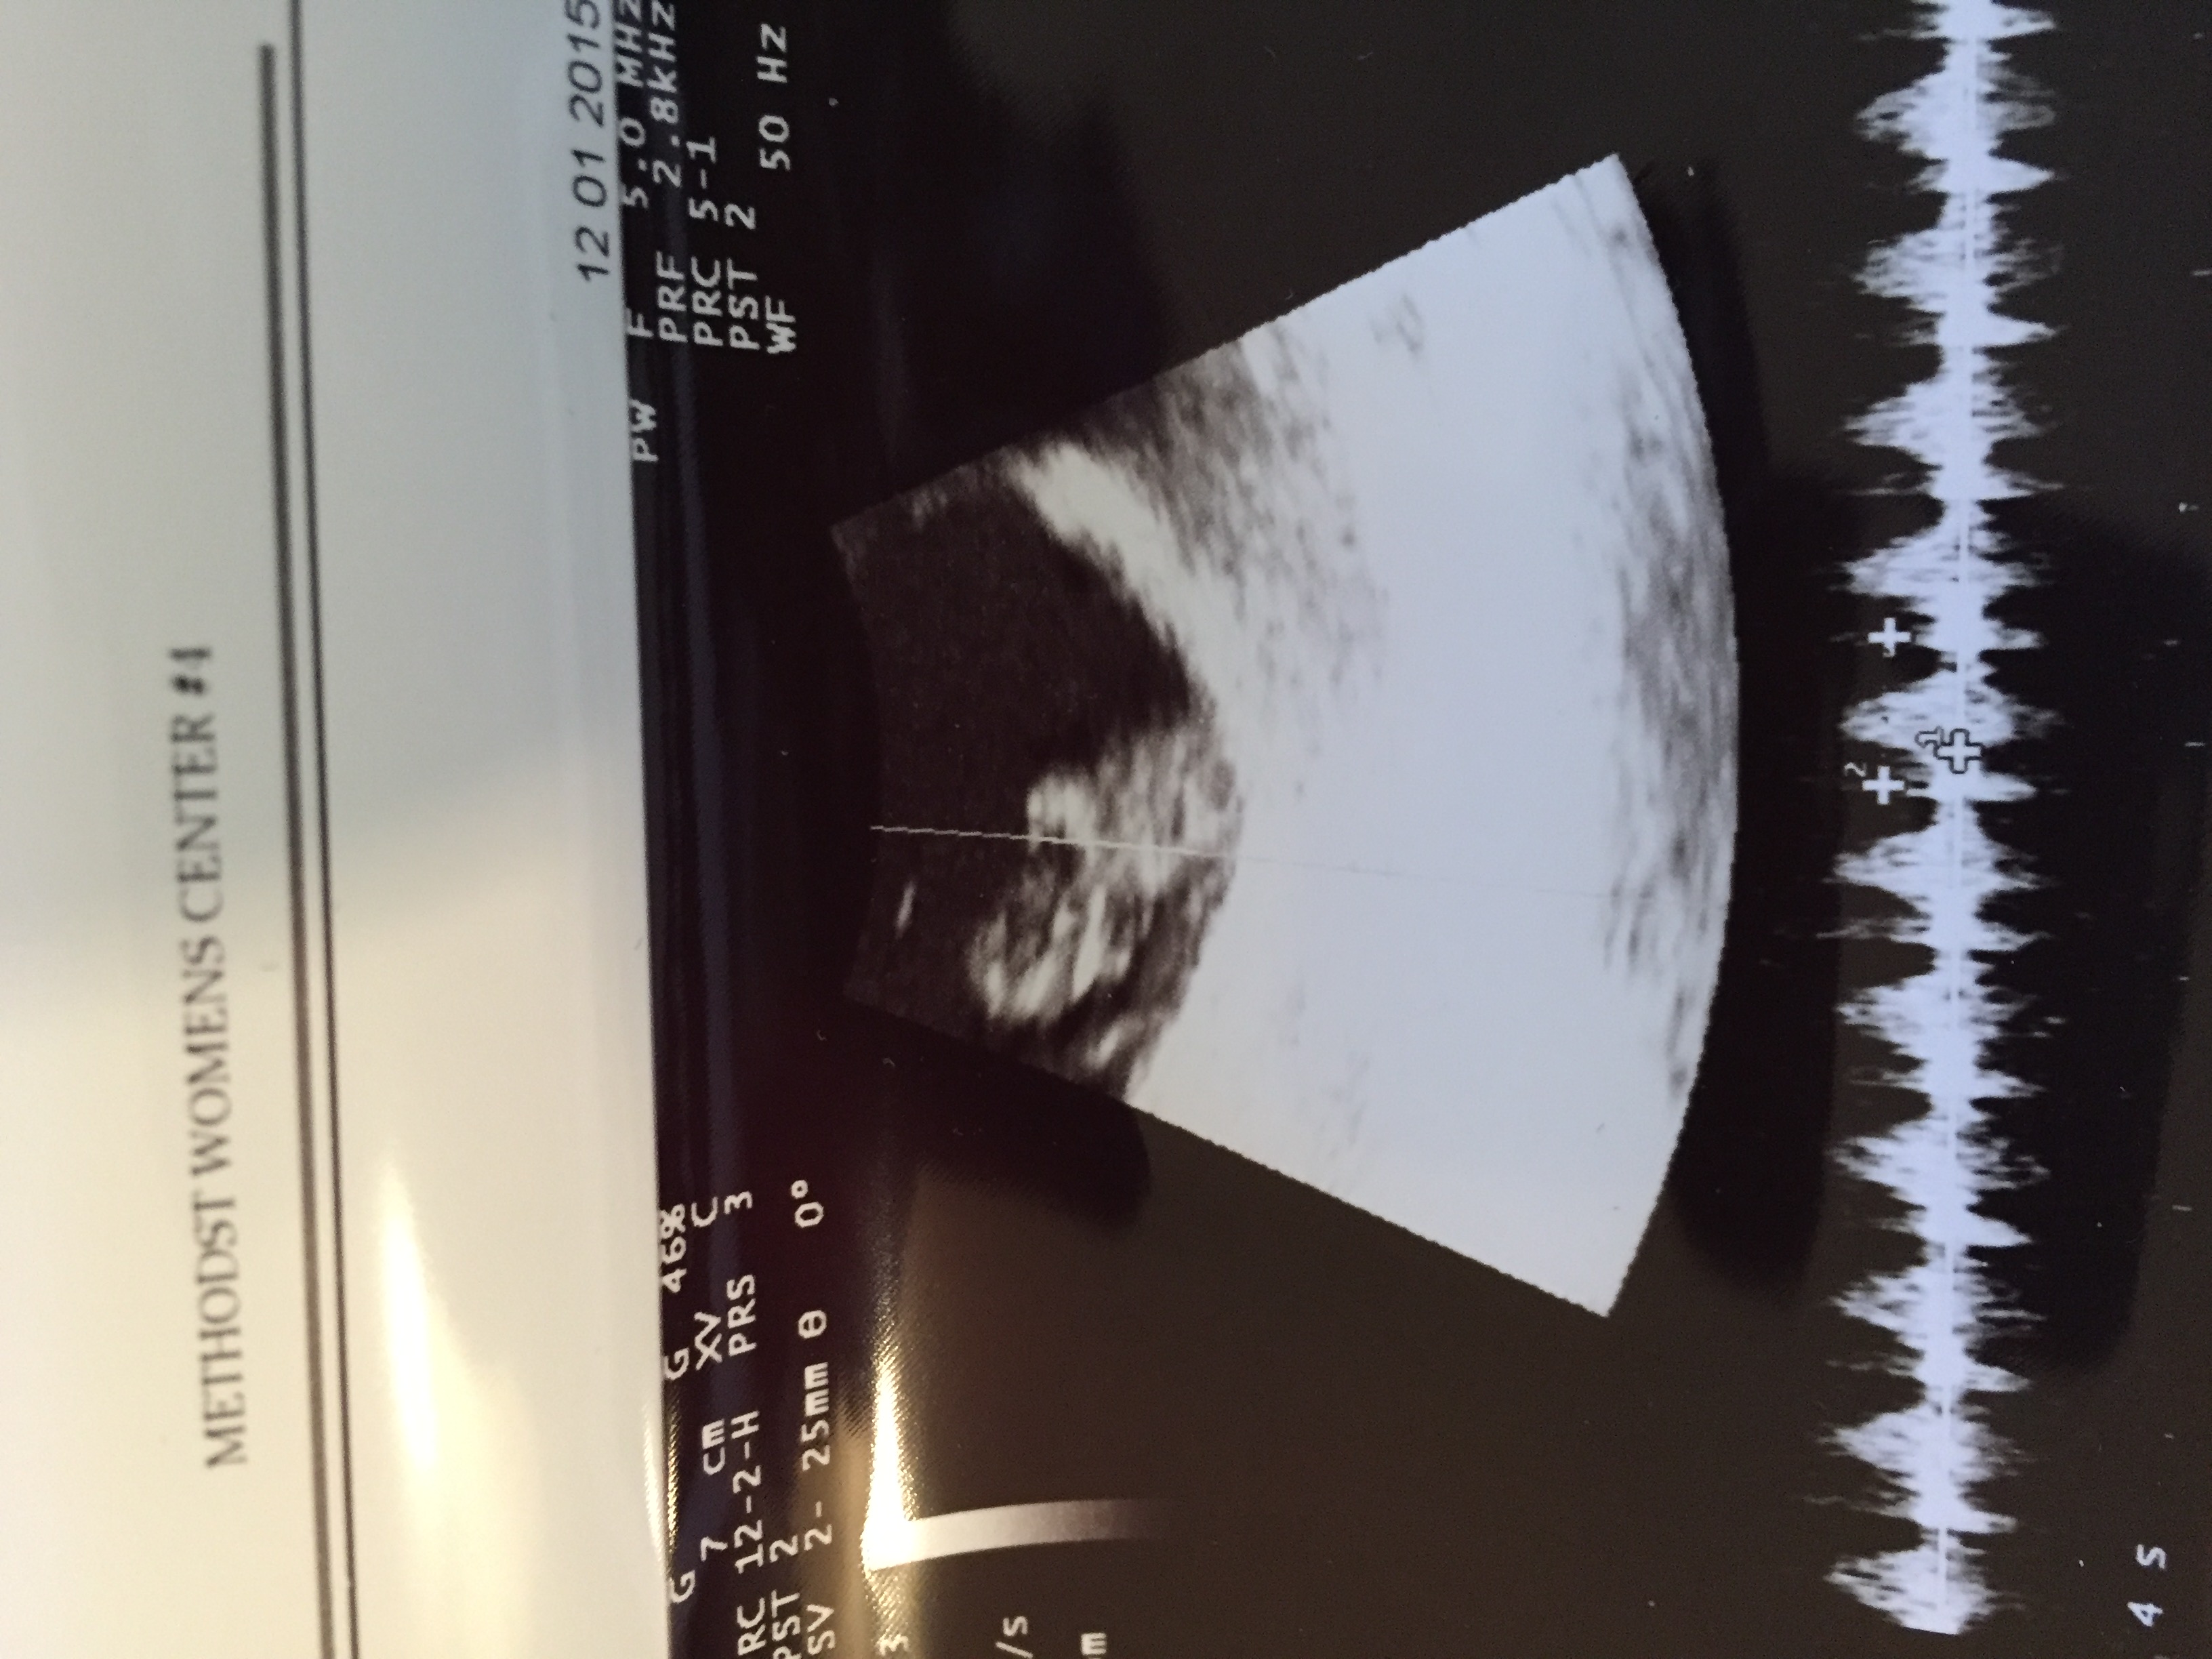

I had my second u/s on Tuesday at 8 weeks and 6 days. The baby is still measuring three days behind but they have not changed my edd. It was great to see how big the baby has gotten and to see its heart still beating. I go back on the 23 for some genetic testing and I get an u/s at that appointment, which was a great surprise to hear that. The equipment at the new place I have to go to is so much better than what my doctor has. Im hoping I can actually hear the heart beat at that appointment. I have not been able to hear it or to know how many bpm it is. But here is my little bean!

Btw I have no clue what those white lines are and neither does my doctor.